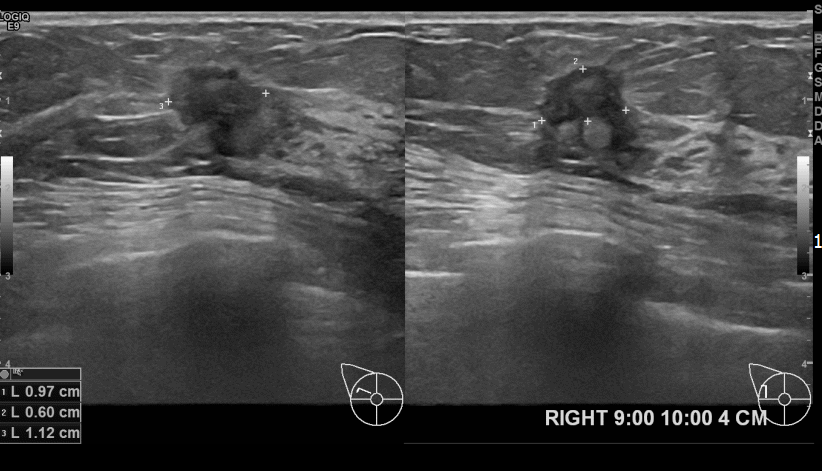

상기환자 외부검진상 이상소견으로 내원하신 70대 여성분으로 우

측유방멍울 조직검사 시행 후 유방암 진단되었습니다.